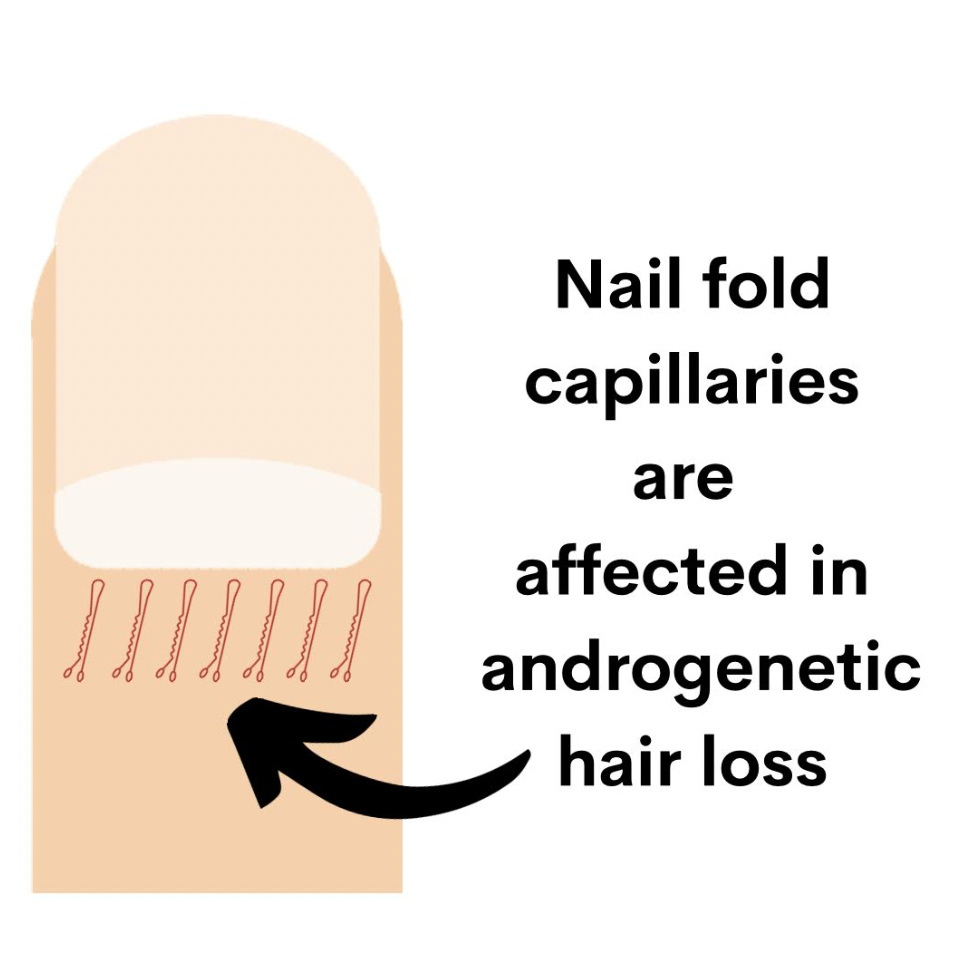

One of the ways to examine the microcirculation of blood vessels is to examine nail fold capillaroscopy changes.

Authors from China set out to investigate whether there are alterations in nailfold capillaries in androgenetic alopecia patients compared to control patients. In addition to examining the type of abnormality a semi-quantitative rating scale was adopted to score the observed capillary abnormalities (0, no changes; 1, <33% capillary alteration or reduction; 2, 33–66% capillary alteration or reduction and 3, >66% capillary alteration or reduction).